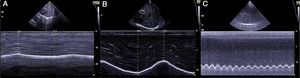

The ability of the diaphragm to generate volume changes in the rib cage is evaluated by measuring its movement. When the subcostal approach is used, a low-frequency convex transducer is placed at the level of the mid-clavicular line, seeking the posterior third of the diaphragmatic dome in the right side, through the liver window. In the left side, the splenic window is used, but the dome is more difficult to locate, especially in the presence of interposing abdominal viscera.6 An alternative is the lateral approach, placing the probe in a perpendicular position in the intercostal spaces below the level of the mid-axillary line. After the dome is located in 2D mode, anatomical M mode ultrasonography is used to help identify the portion of the dome with greatest mobility, which is then measured in a sagittal slice. Respiratory movement is measured at rest (tidal volume), in deep inspiration and expiration (vital capacity), and in sniff maneuvers (Fig. 1). The force of the movement can also be measured (movement over time, visualized as the slope of the movement curve). In some situations in which the diaphragm is not properly differentiated, the movement of abdominal viscera can be measured (vena cava in the right side, or the spleen on the left), with acceptable results. This is known as the “indirect method”.7

Measuring diaphragmatic thickness is another method currently used to determine diaphragmatic muscle mass and assess the thickening fraction (TF). For this measurement, a high-frequency linear transducer is used, placed between the last intercostal spaces. This locates the zone of apposition, where the diaphragm is in direct contact with the chest wall. The diaphragm is identified as a hypoechoic strip flanked by two hyperechoic lines, which correspond to the pleura and peritoneum. The TF is the ratio between diaphragm thickness at rest (functional residual capacity) and in maximum inspiration (vital capacity) (Figs. 1 and 2).